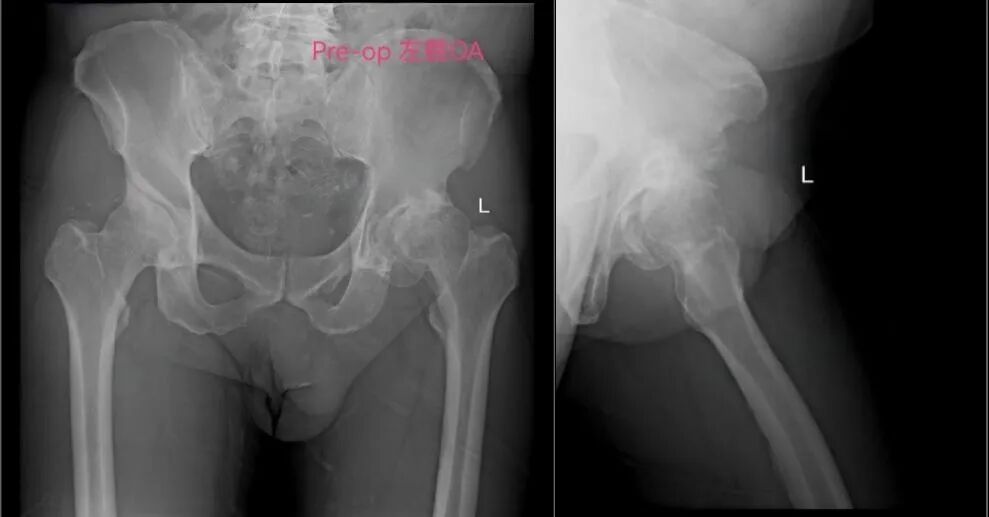

梁大爷多年来饱受左髋关节重度骨性关节炎困扰,行走困难,生活质量严重下降。尽管人工髋关节置换术是有效治疗手段,但因对手术创伤大、恢复慢、风险高的固有印象,手术一直成为他心中的“噩梦”。加上梁大爷有心脏基础疾病,手术与麻醉风险较高,进一步增加了治疗难度。